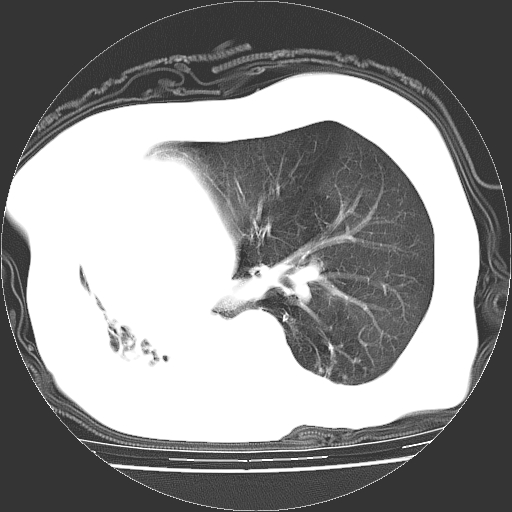

标题: CT23991:女,72岁,咳嗽、憋气一周。 [打印本页]

女,72岁,咳嗽、憋气一周,十年前曾患肺结核及胸膜结核。

右侧毁损肺,右侧纵隔疝

右侧毁损肺,右侧纵隔疝,左肺代偿!

右侧肺硬变,左肺代偿气肿。

1.右侧损毁肺伴胸膜钙化,2.左肺小结节灶,良性可能大,注意复查。3.肝脏左叶囊肿。4.先天性一侧肺不发育待出外(右侧胸廓无明显塌陷)。对比原片应该非常有帮助。

右侧肺毁损,左肺代偿性肺气肿,纵隔疝。